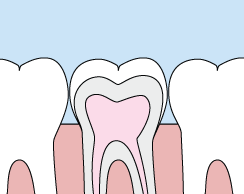

Crowns

Services provided by General Dentists.

Crowns are a restorative procedure used to improve your tooth’s shape or to strengthen a tooth. Crowns are most often used for teeth that are broken, worn, or have portions destroyed by tooth decay.

A crown is a "cap" cemented onto an existing tooth that usually covers the portion of your tooth above the gum line. In effect, the crown becomes your tooth’s new outer surface. Crowns can be made of porcelain, metal, or both. Porcelain crowns are most often preferred because they mimic the translucency of natural teeth.

Crowns or onlays (partial crowns) are needed when there is insufficient tooth strength to hold a filling. Unlike fillings, which apply the restorative material directly into your mouth, a crown is fabricated away from your mouth. Your crown is created in a lab from your unique tooth impression, which allows a dental laboratory technician to examine all aspects of your bite and jaw movements. Your crown is then sculpted just for you so your bite and jaw movements function normally once the crown is placed.